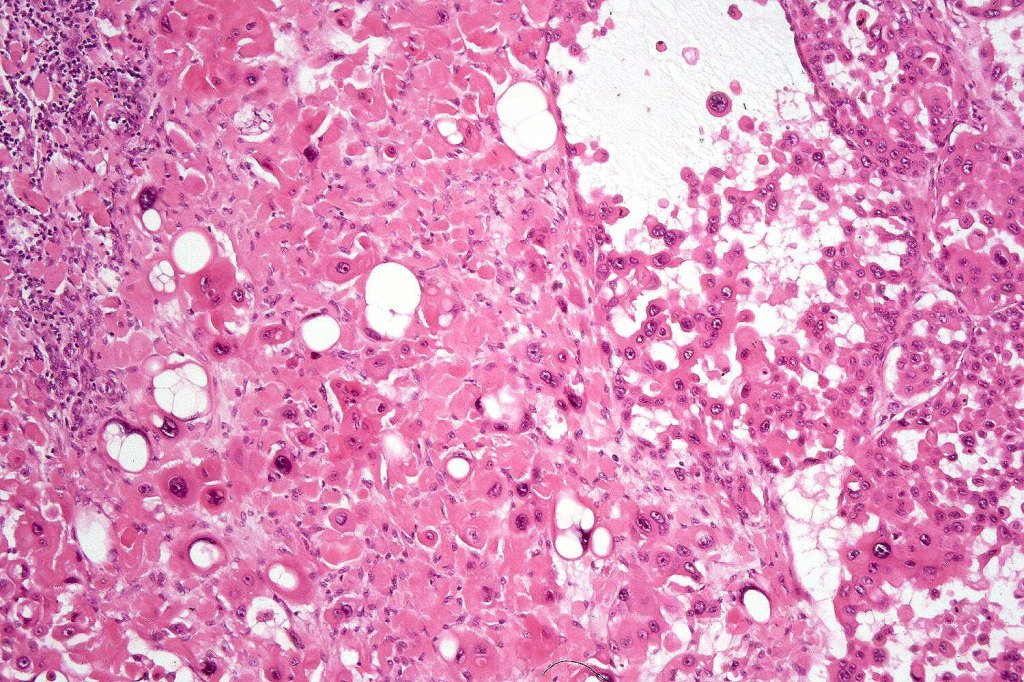

•Acantholysis gives rise to a pseudoglandular appearance

•Variable pleomorphism & mitotic activity

•Amyloid may be present

•Exceptional associated signet-ring cell change (signet ring cell squamous carcinoma)